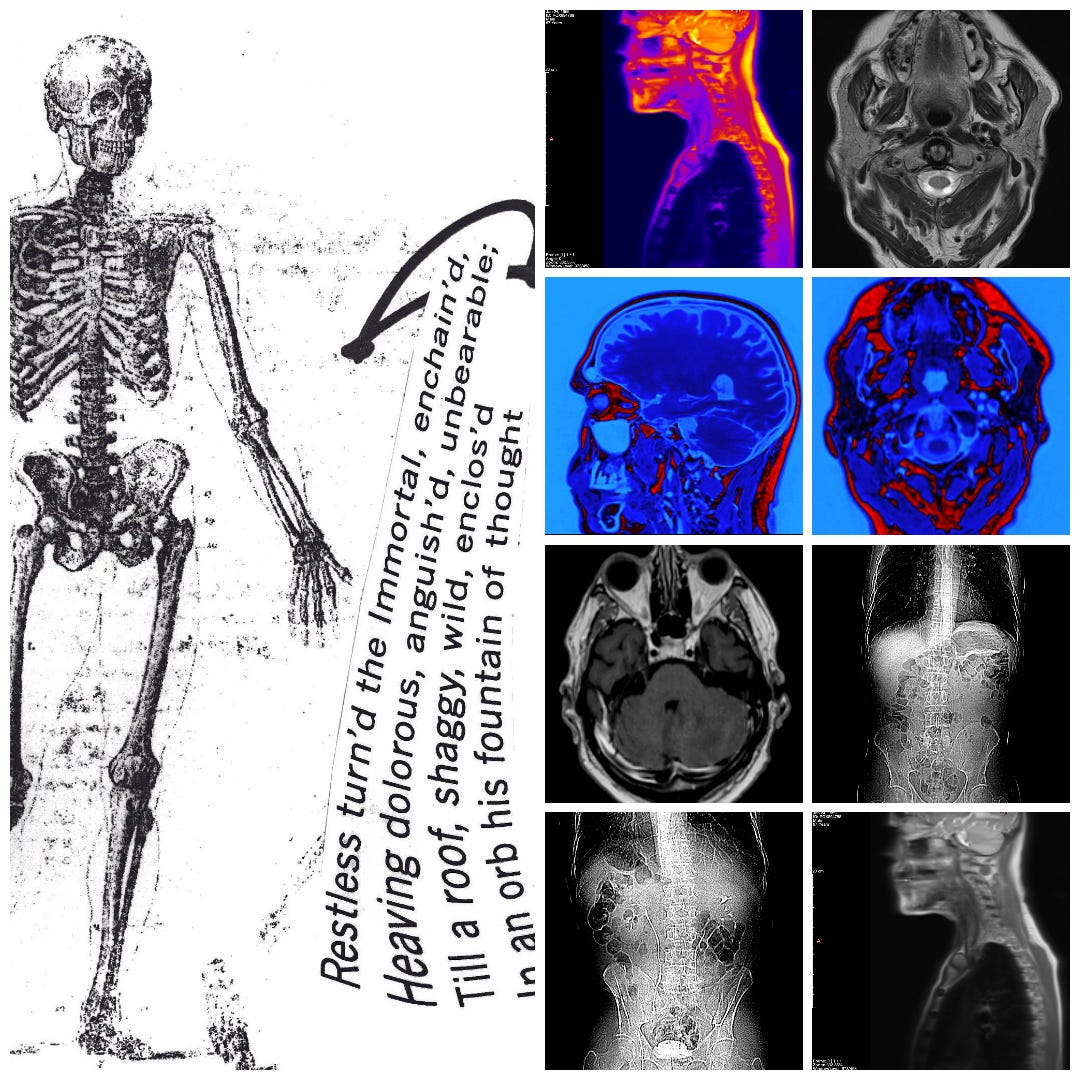

This post concerns an impending death; my own. My recent diagnosis (Mar 4ᵗʰ) is both complicated, but also typical of a stage four lung cancer (metastatic cancer), if I understand it right, with the cancer identifying itself only weeks ago, and further growths identified since then: I have tumours in the legs, lymph nodes and adrenal glands; a 4.5 cm tumour on the left lung is crowding out the nearby aorta; it has sprouted a smaller (11 mm) tumour on the right lung too; and colonies have set up camp in the cerebellum. A round of CT (Computed Tomography), MRI (Magnetic Resonance Imaging), X-Ray, EBUS (Endobronchial Ultrasound), and PET (Positron Emission Tomography) scan results is still being analysed. New facts emerge. I’m only just weeks into things and counting.

A PET scan is organised a few days later, at St Barts Hospital, in the shadow of St Paul’s. The body is flooded with a tracer radioactive fluid, after which you are locked into a lead-lined box for three-quarters of an hour to allow it to bake in. The scanner then detects where the tracer has been absorbed by cell growth anywhere in the body it is directed, producing reams of flowing light captured to film, copies of which—scans of my own body—are used throughout this post.

bodies of light

The moment I saw the very first scan the doctors showed me (bottom right, above: an MRI, rather than PET, as it happens)—on a small monitor wheeled into my cubicle at the Homerton—seemed to say everything at once. As I turned my head to look at the image of my brain on the monitor, I glimpsed also the tattoo on my left arm suddenly aligned with it (bottom left)—a tattoo of a bhikkhu meditating in flames, inked twenty years earlier, with the bhikkhu meditating as descibed in the Buddha’s Adittapariyaya Sutta (Fire Sermon)—such that the tattoo of the bhikkhu and the scan of the brain, aligned properly. One presaged the other by years, holding out its hand to the other. They reflected each other so neatly, with the tumour in the cerebellum showing up as the red-orange fire bursting through from within, which the bhikkhu sits through.

The wrinkled surface of the cerebral cortex in the scan echoed the Bhavachakra—the wheel of Saṃsāra, of cyclical existence (“Saṃsāra… is a Sanskrit word that means ‘wandering’ as well as ‘world’, wherein the term connotes ‘cyclic change’ or, less formally, ‘running around in circles’)10—against which the bhikkhu rests in the tattoo. Here is an image, not only of that empty time turning that we have talked of, of cyclical return and, dare I say it, reincarnation (though in this formulation, reincarnation is mere repetition, as in the ‘natural’ repetition of pagan society). In the original Fire Sermon, the argument is that the bhikkhu must free themself from the grasping tyranny of the senses. We, on the other hand, will be moving in the other direction. In any case, this combined image almost made me fall out of bed.

On seeing further scans, I recognised, eg., my rib cage as something indeed very much like the frame of Israel’s tents (above, top left), beaming on the shore of the infinite (Blake), but also, in the twisting images of the torso, I am struck by the sprawling energies at play, unleashed by disease. No longer is there the assumed underlying durable person, sealed away from the totality, cybernetically establishing their personal border by fending off and repurposing the chaos, sickness and disorder without. Instead, raw energies start to coalesce, turning Urizenic, mechanical rigidity into flashes, streaks and pulses of contending light.

When looking at the flowing lights of the scans, I am not seeing the regular mechanics/dynamics of fluid flow and the like. It is not the competing power of the different forces involved, sloshing against one another, that impresses. That would represent a reasonable romantic regard for the power of things we don’t fully understand, and which we dimly suspect may outbid us in the end.

What I find more compelling in the forms on show are the signs of a deeper, primordial language of the cosmos, God’s being and the unconstrained underpinning of all those other things, the syntax of God’s mind and its reality of eternal esemplatic (form-giving, creative) inflation. To see the churning faces of the sea of light is to see the surface of the esemplasm that is all being, and which calls us from its depths.

scarlet rain falling: libelling the dead

In looking at the scan images in this post, try to imagine just how surprised I have been to realise that some 2-3 years ago I started working on a long (for me) poem/collage construction, which, for reasons I cannot explain (are there ever any such tidy reasons), I called Scarlet Rain. I have worked on it patiently for some time now.

You will see from the examples above that I am soon talking of lungs and jaws, ‘Easington irradiation’, blooming bones and the ‘undead bloodsuck’. The work currently stands at more than seventy pages, but remains unfinished. It includes many vignettes and side glances at my family history, as well as thoughts on ‘libelling the dead’.